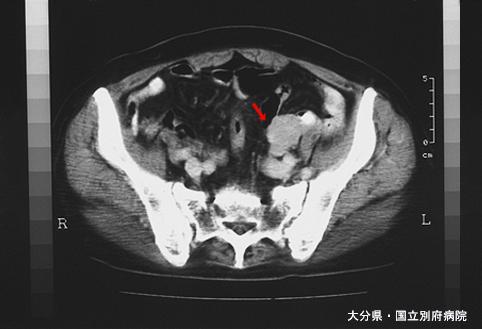

症例提示(所在地,施設名等): 大分県・ 別府医療センター ( Dr.松尾ら)

疾患(病理主体)の分類悪性非上皮性腫瘍/平滑筋肉腫(含GIST)

部位(臓器別)小腸/回腸

検査方法CT

病変の最大径(ミリ)25〜29

多発腫瘍(同一臓器)有(同時性)